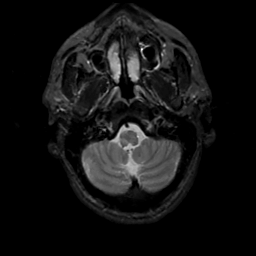

MR Study #6, March 17, 1991 -- Slice #6